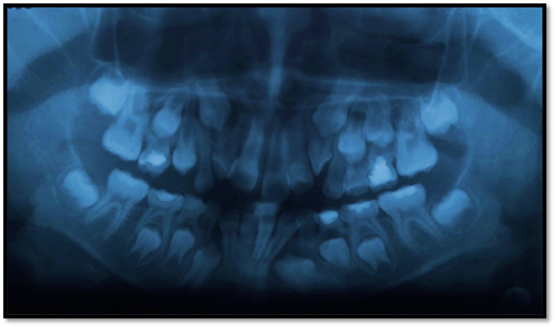

Paciente de 8 años de edad de sexo masculino, acude a la clínica odontológica acompañado de su mamá, solicitando tratamiento de ortodoncia. Al examen clínico extraoral se evidencia en una vista frontal simétrico sin alteraciones; en el examen clínico intraoral se evidencia un aumento de volumen entre las piezas 2,2 y 6,3, el mismo que mide aproximadamente 2 mm de ancho por 3 mm de largo, a la palpación de consistencia dura, mucosa adelgazada, color blanquecino y asintomático (Figura 1).

Figura 1: Fotografía extraoral e intraoral se observa la mucosa adelgazada y blanquecina por la presencia del incisivo suplementario.

Como protocolo de diagnóstico se solicita radiografía panorámica, donde se observa a nivel intraóseo entre las piezas 2,2 y 6,3 una estructura dentaria de forma cónica, imagen compatible con un diente supernumerario de tipo conoide, el mismo está localizado por debajo del canino permanente lo cual a la larga iba a impedir su erupción (Figura 2).

Figura 2: Radiografía panorámica (Circulo, lugar de la pieza supernumeraria).